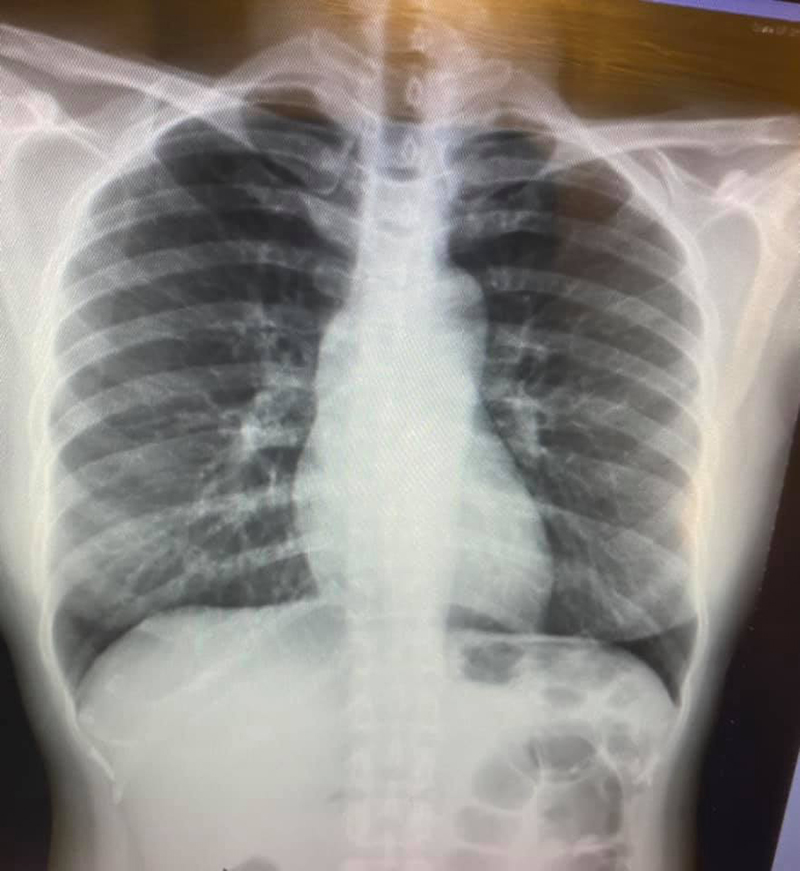

กลับมาสู่เรื่องของเรากัน ดังนั้นในฐานะแพทย์ระบบภูมิคุ้มกันเลยได้ทำการตรวจหาภูมิคุ้มกัน Neutralizing antibody ของตัวเอง เพื่อจะได้เข้าใจระบบภูมิคุ้มกันของตัวเองต่อการตอบสนองต่อวัคซีน (การไม่มีคำแนะนำว่าตรวจภูมิคุ้มกันแค่ไหนถึงป้องกันได้ ก็ไม่ได้หมายความว่าไม่ควรจะตรวจ เพราะว่าถ้าไม่ตรวจและเก็บข้อมูลก็จะไม่มีวันรู้สักทีว่าระดับเท่าไหร่ถึงจะพอจะป้องกันได้) ดังนั้นหลังฉีดวัคซีน Sinovac ครบที่ 2 สัปดาห์ ตัวเอง ก็ได้ตรวจระดับ NAb ซึ่งก็สูงถึง 92.9% แต่พอติดตามไปหลังฉีดวัคซีนครบที่ 2 เดือน ค่า NAb ลดลงมาเหลือ 65.7% และในช่วงที่ค่า NAb 65.7% ก็เป็นช่วงที่ตรวจ COVID-19 detected ที่ Ct 18 โดยคาดว่าการติดเชื้อนี้ได้มาจากการ Contact positive case ในห้องแล๊ป เย็น อากาศปิด นานประมาณครึ่งถึงหนึ่งชั่วโมง ในขณะที่ตัวเองใส่ N95 ค่ะ ใช่ค่ะ N95 (แต่ no Faceshield) และก่อนหน้าที่จะเข้าไปใช้ห้องแล๊ปนี้มีคนที่มาใช้เครื่องมือที่มีอาการไอค่อนข้างมากอยู่ก่อน และจากการได้รับอาหารมาจากเคสที่บวกเหมือนกัน แล้วไปแยกนั่งกินกันคนละห้องกัน ข้อสำคัญคือเคสที่บวกด้วยกันก็ฉีด Sinovac ครบ 2 เข็มเรียบร้อยและเช็ค NAb อยู่ที่ 60.04%

สิ่งเหล่านี้บอกอะไรเราบ้าง บอกว่า COVID 19 รอบนี้ติดง่ายมากๆค่ะ คนที่ฉีดวัคซีนครบทั้งสองคนที่มีภูมิคุ้มกันขึ้นทั้งคู่ก็สามารถติดเชื้อได้หรือแพร่ให้กันได้หรือในที่อากาศปิดเย็นที่เคยมีคนติดโควิดแพร่เชื้อไว้ก็ยังสามารถติดได้ real world data (ประสบการณ์ตรง) ที่เมื่อฉีด Sinovac ไปเพียง 2 เดือน ก็มีภูมิคุ้มกันที่ลดลง (ซึ่งไม่ถึงกับหายไปเลยนะคะ ก็แค่ลดลง 30%) แต่ก็ตำ่พอที่จะไม่สามารถป้องกันการติดเชื้อสายพันธุ์กลายพันธุ์ได้ค่ะ (คิดว่าเราน่าจะโดนสายพันธุ์ Delta แน่ๆเลย) ดังนั้น Sinovac ไม่กันติดเชื้อนะคะ confirmed กับ real world data อื่นๆทั้งในและนอกประเทศ ส่วนตัวขอแนะนำให้แพทย์และบุคลากรทางการแพทย์ทุกคนตั้งการ์ดสูงๆเข้าไว้ ใครที่ฉีด Sinovac ไป 2 เดือนแล้ว ภูมิคุ้มกันคงเริ่มลงแล้วค่ะ (ตัวเองฉีดครบหลังสงกรานต์ค่ะ) พยายามตรวจคนไข้ Telemedicine ให้มากเท่าที่จะทำได้นะคะ และแนะนำใส่ N95 ตรวจคนไข้ในห้องแอร์ Faceshield ด้วยก็ดีนะคะ ส่วนคนอื่นๆ work from home ได้ทำนะคะ ตัวเองอยาก Work from home มากกกกก แต่ด้วยลักษณะงานทำให้ไม่สามารถทำได้

แล้ว Sinovac กันอาการรุนแรงได้ไหม (เพราะดูจากค่า Ct ที่ 18 ก็แสดงว่าปริมาณเชื้อในตัวเราก็น่าจะเยอะพอควรค่ะ) อันนี้จะมาเล่าให้ฟังครั้งหน้าว่าอาการเราเป็นอย่างไร (ถ้ารอดมาได้นะคะ 555)